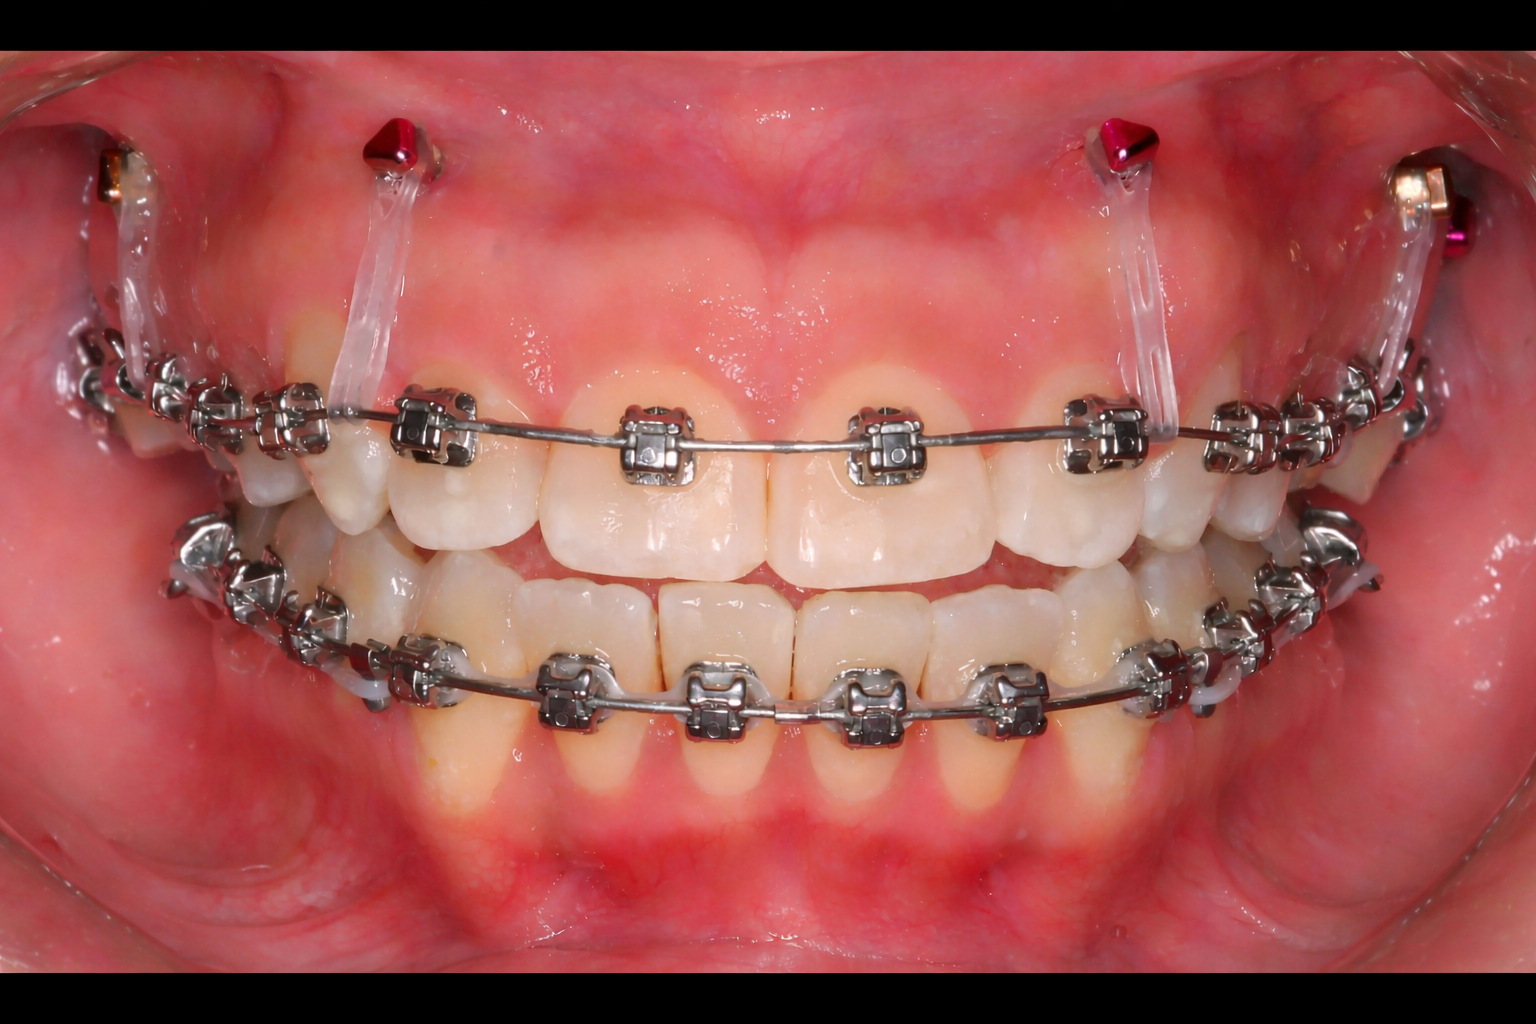

Orthodontic TAD mini-screw placement in clinic by Dr Benguira

Orthodontic TAD mini-screw inserted in the gum for skeletal anchorage